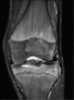

Microfracture

Microfracture surgery is an articular cartilage repair surgical technique that works by creating tiny fractures in the underlying bone. This causes new cartilage to develop from a so-called super-clot. [Source: Wikipedia ]